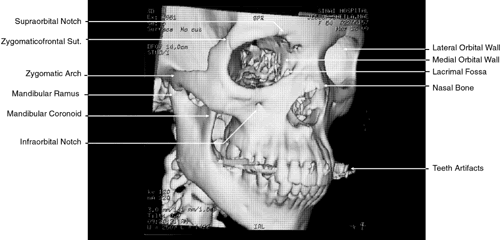

More recently, evolution in CT software has permitted the creation of high-resolution 3D images (Fig. 1).8 This has been of particular interest in cases of traumatic and congenital bony defects of the skull, where such images are quite useful in planning reconstructive efforts. With additional mathematical manipulation of the attenuation coefficients obtained from cross-sectional 2D slices, 3D images can be reconstructed. This is accomplished by estimating the interstice voxel HU values. These are generally assumed to be a weighted average of the HU values for the voxels of the two adjacent slices. The locations of the voxels are then described in terms of a 3D coordinate system with the z-axis parallel to the CT scanner table, the y-axis perpendicular to the top of the table, and the x-axis parallel to the CT scanner gantry opening. These images can then be reconstructed in either gray-scale or false color and recorded on film or tape.

Fig. 1. Three-dimensional computed tomography reconstruction of facial bones and orbit.